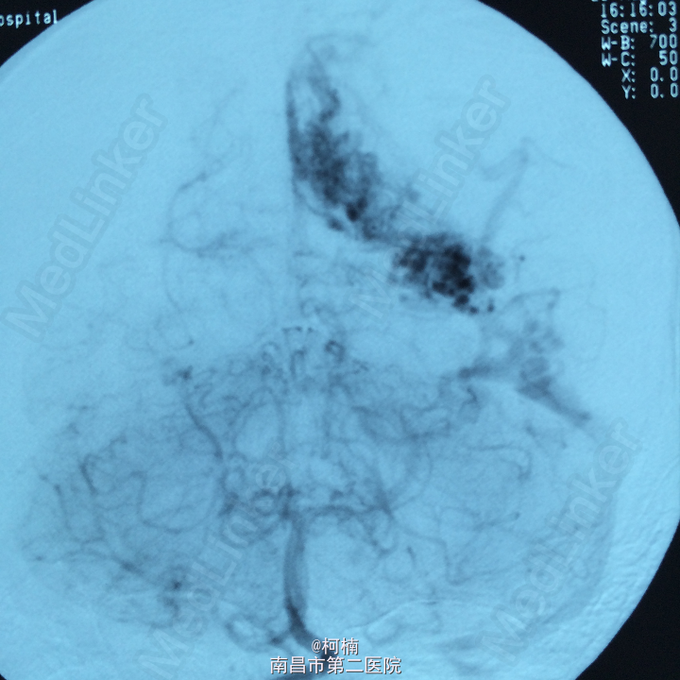

诊断:脑动静脉畸形 处理:予急诊行DSA检查,提示脑动静脉畸形,予行血管内栓栓塞治疗